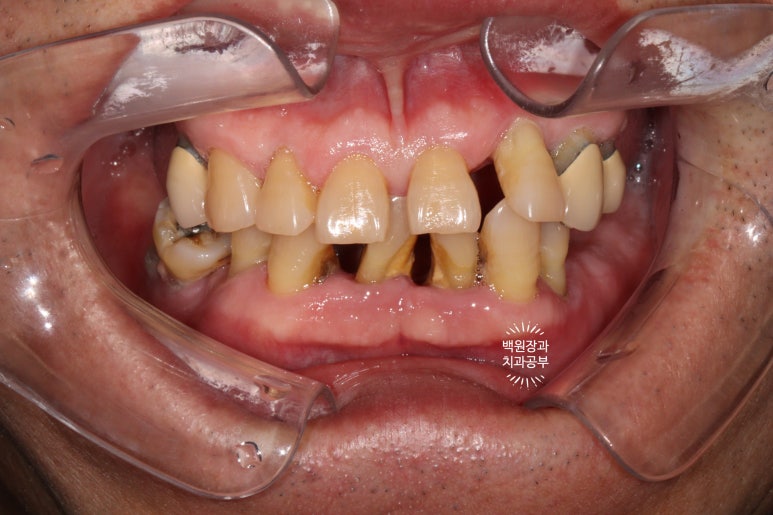

정면에서 찍어본 구강 내 사진 소견입니다.

다수의 치은연상치석, 치은연하치석이 침착되어 있고, 만성치주염으로 인해 치아가 제 위치를 상실하여,

치아의 병적이동 (pathologic migration)을 하고 있는 중이었죠.

풍치가 심해서 만성치주염을 오래 앓으신 분들은 치아 사이가 벌어져 심미적으로 불리한 모습을 많이 보이십니다.

게다가, 어금니들도 씹는 면끼리 물리지 못해서 이제 식사도 어려우신 상황이었어요.